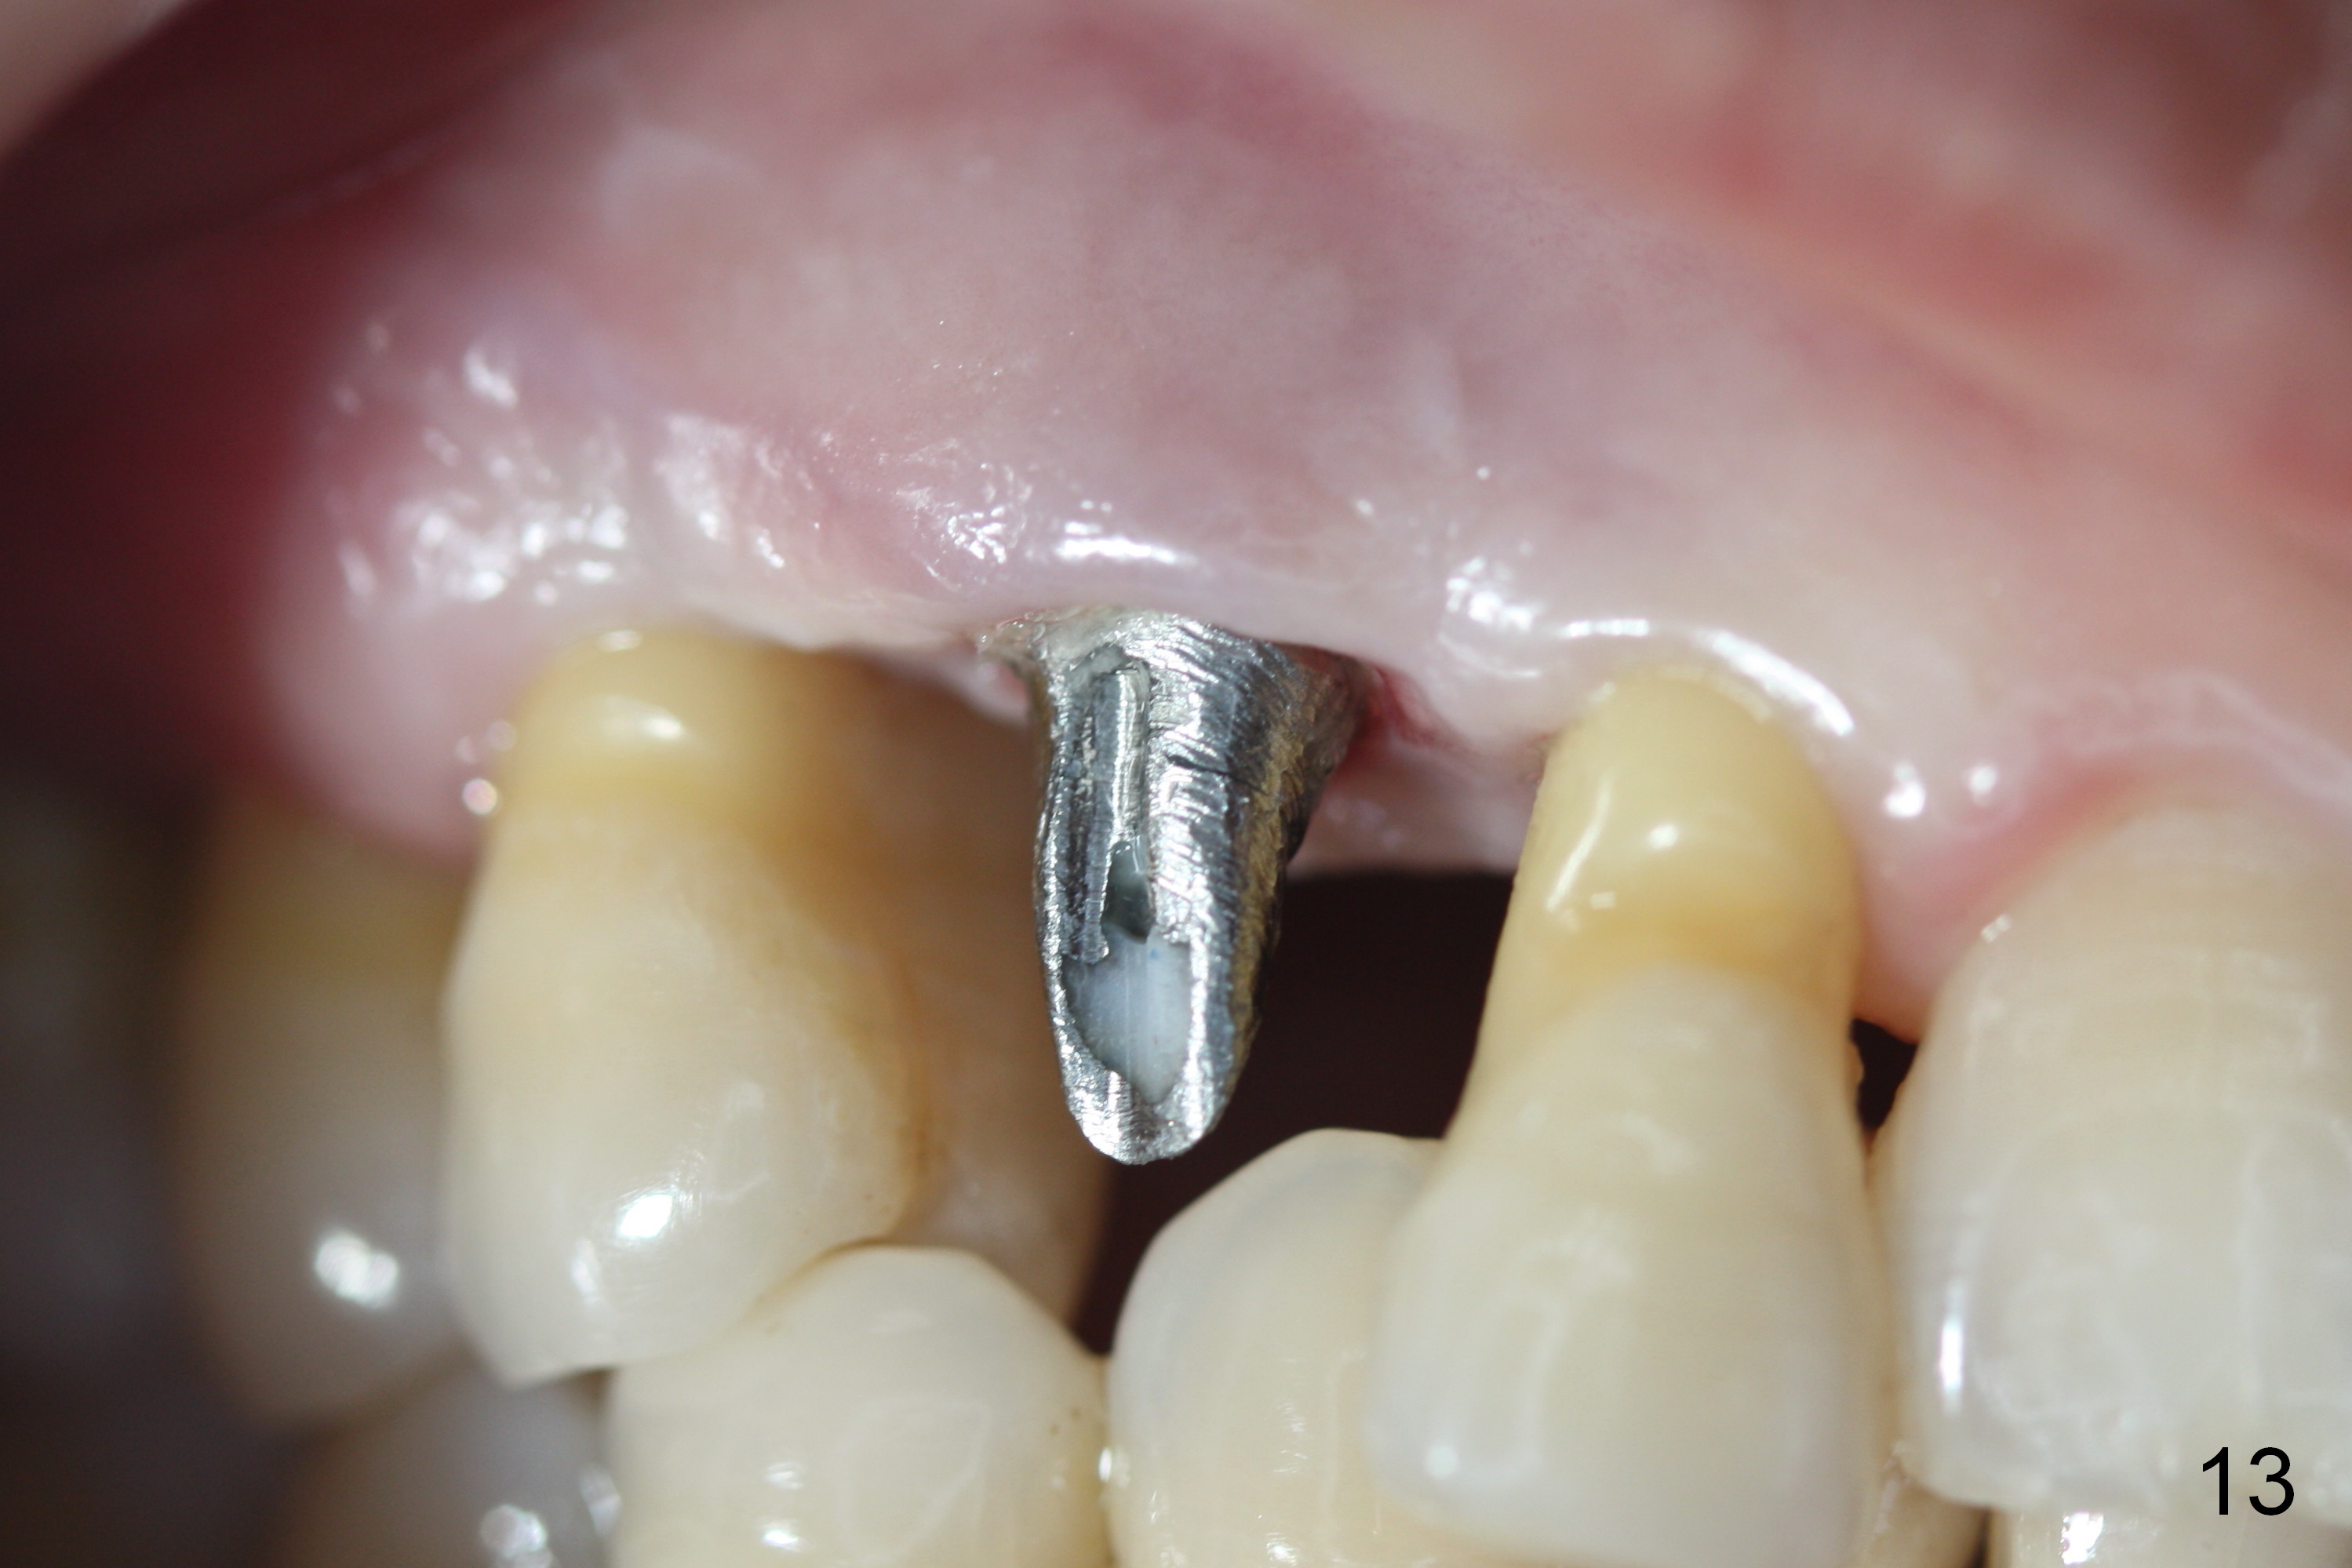

Four months post implant placement, the immediate provisional (Fig.1 P) has mobility with tenderness and perforation at the cervix (^). When the provisional is removed, the buccal plate bulging is more evident (Fig.2 arrowheads). The latter is apparently caused by bone expansion associated with implant placement (Fig.3 black *), since the bulging is not so obvious in a preop CBCT 3 D image (Fig.4 *). There is a layer of fiber granulation tissue (Fig.3 white *) around the mobile implant (I). More fiber tissue is noted when the implant is removed (Fig.5). A new osteotomy is created in the palatal wall of the existing implant site with 2 mm pilot drill, followed by 2.5 and 3 mm reamers. As a 4.5x17 mm tap is being inserted (Fig.6 T), it is deviated buccally. Reamers are re-used to try to remove more palatal bone to let the implant be placed more palatally. When a 4.5x17 mm tissue-level implant is placed (Fig.7,8 I with insertion torque >60 Ncm), there is a small buccal gap (Fig.8 *). A 20° angled abutment (Fig.7,8 A) is placed. An immediate provisional is fabricated with cosmetic satisfaction.

The gingiva is healthy 6 months postop (Fig.13) without buccal plate collapse (Fig.14). The implant and abutment have been prep for final restoration (Fig.15). Although the buccal plate is thin 3 years 5 months post cementation (Fig.16 B), the crest (>) is present, which accounts for no periimplantitis.